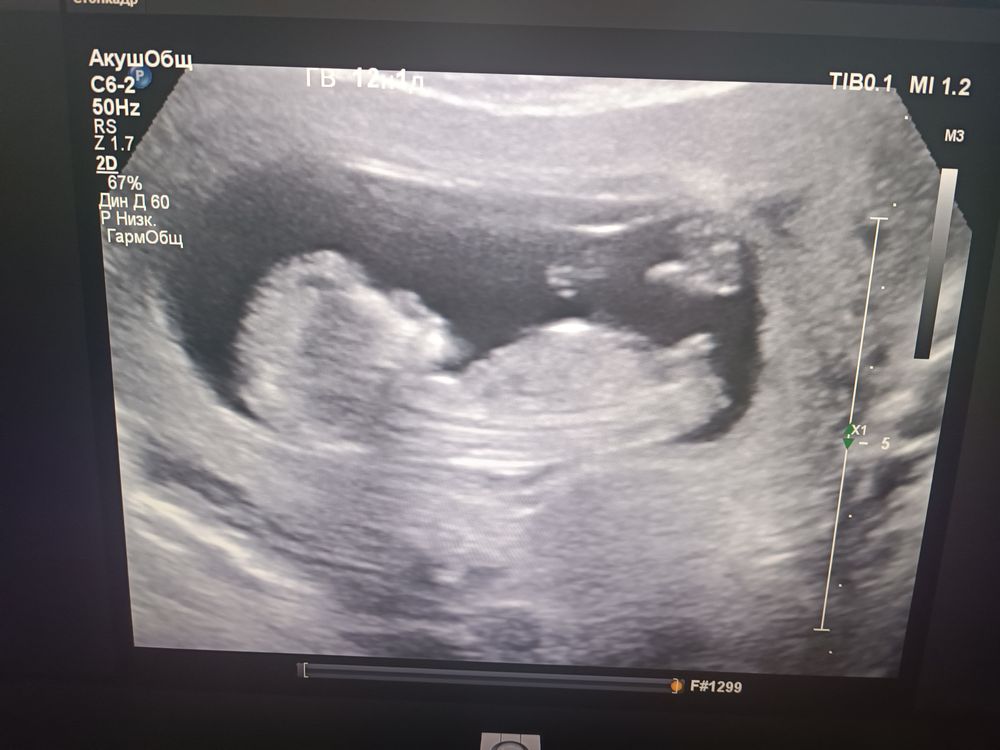

Девочки, я обещала обязательно сообщить результаты гендер-пати,вчера провели,на руках фото ещё нету,но как оказалось мы ждём второго мальчика))) Я буду дважды свекровью! Для тех, кто думает проводить или не проводить такое мероприятие могу сказать,что оно однозначно того стоит)) Эмоции били через край! Так что,если кому-то наши фото помогут в дальнейшем определении пола-буду рада помочь)))